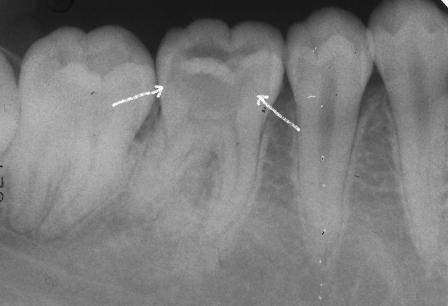

虫歯の穴は小さく、ほとんどピットでしかありませんが、

レントゲン写真では残っているのはエナメル質だけで、

象牙質は溶けだしてしまって、がらんどう、、

虫歯は神経まで届いています。

痛いのは当然でしょう。